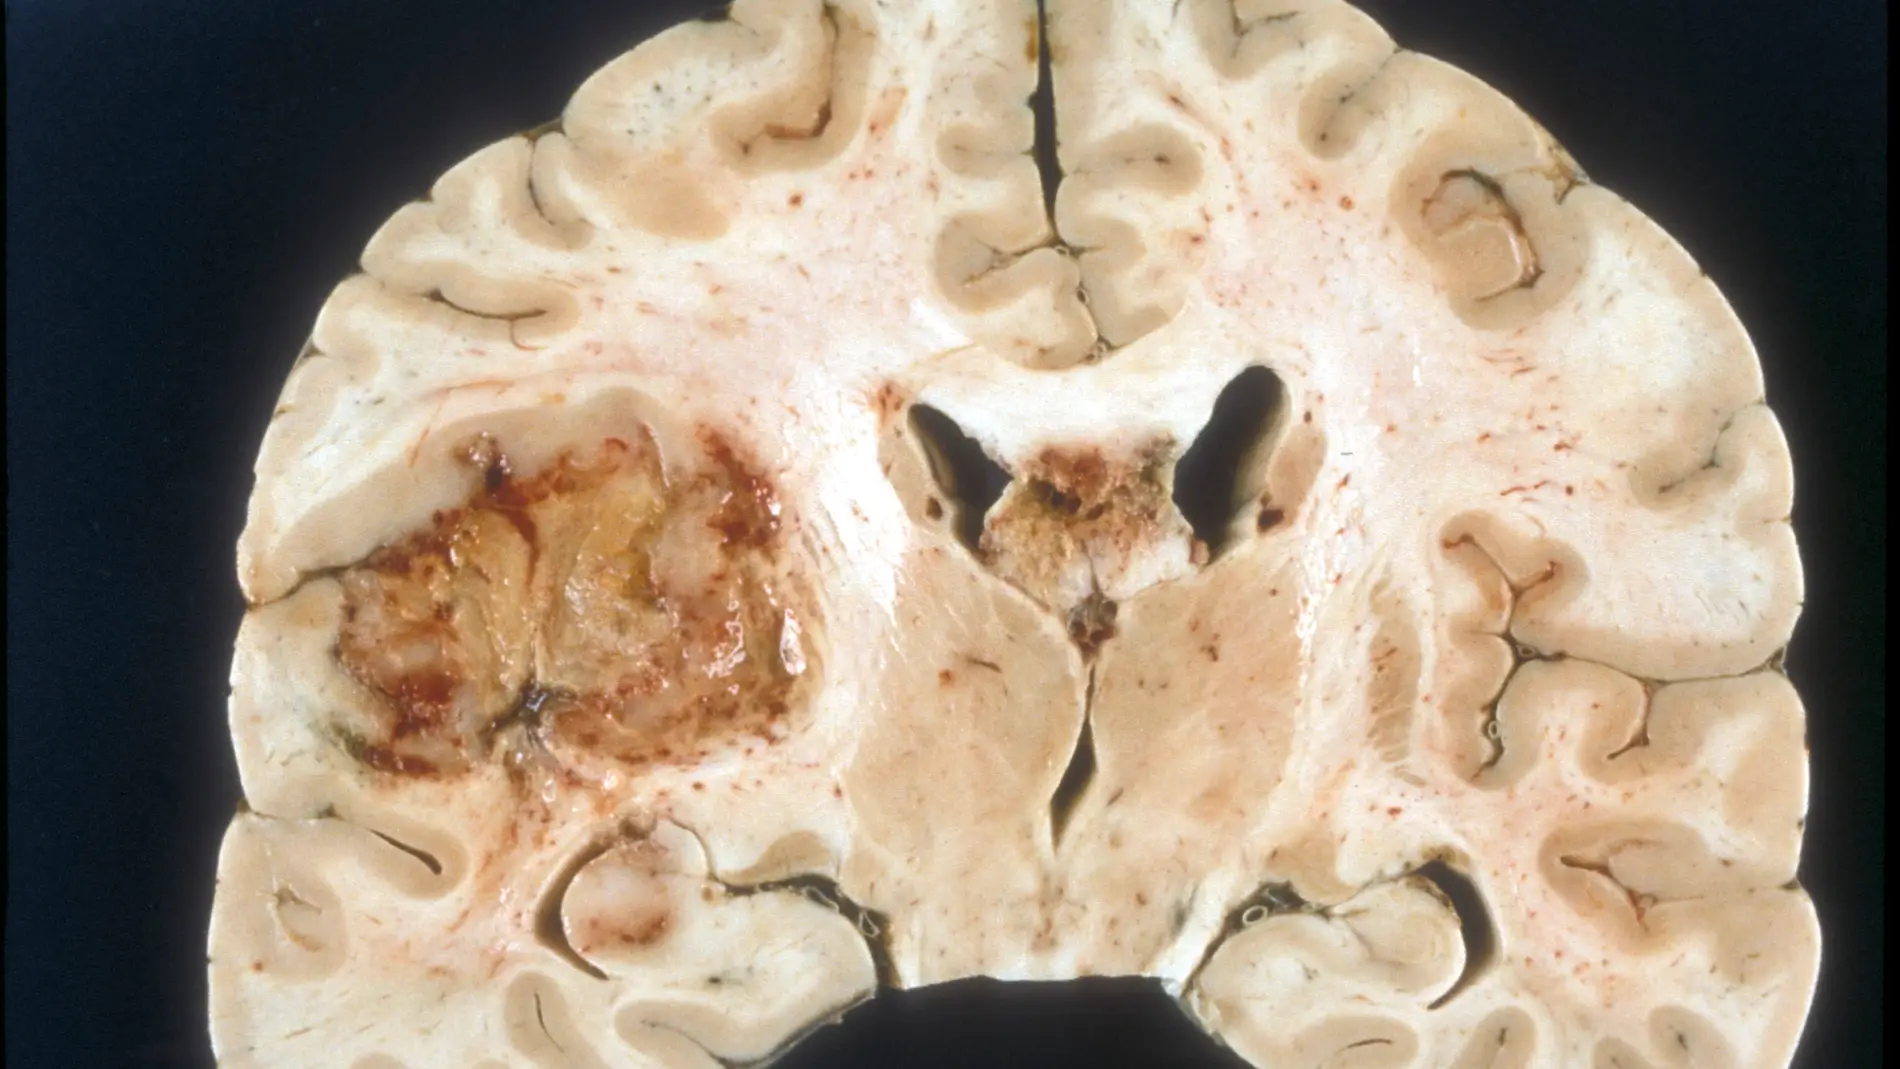

El glioblastoma es la manifestación más agresiva de los tumores cerebrales. Debido a la elevada capacidad invasiva y su crecimiento descontrolado infiltrativo, es un tumor especialmente difícil de tratar. Actualmente, el tratamiento establecido para los pacientes con estos tumores consiste en la combinación de cirugía (cuando es posible), radiación y quimioterapia.

Los científicos han observado que las células de este tipo de tumor albergan un defecto intrínseco común que consiste en una incapacidad para degradar su material genético durante la apoptosis, la forma más importante de muerte celular programada inducida por la radioterapia y por agentes quimioterapéuticos. Los resultados se publican en la revista Neuro-Oncology.

Este defecto está relacionado con una enzima: la endonucleasa activada por caspasas, DFF40 / CAD. Esta enzima, esencial para que la célula degrade su ADN durante la apoptosis, aparece disminuida y localizada de manera incorrecta dentro de las células tumorales en comparación con las no tumorales.

Los investigadores han observado que la sobreexpresión de la enzima permite a las células de glioblastoma degradar correctamente su contenido genómico, de acuerdo a lo que se espera de una muerte celular apoptótica.

La degradación del ADN durante la apoptosis es esencial para que la posterior eliminación de los restos celulares se produzca de forma correcta. De hecho, la falta de degradación y eliminación del material genético proveniente de células malignas podría acarrear consecuencias perjudiciales para el organismo, como el rebrote de nuevos procesos tumorales, a menudo más agresivos que el original.